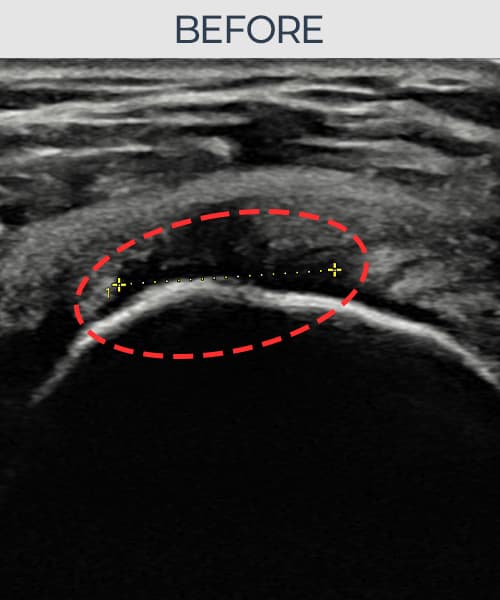

시술 전 초음파 측정 결과 파열 크기는 9mm × 5mm (힘줄 두께의 약 50% 결손)로 확인되었습니다. 시술 전 초음파에서 관절면측(articular-side) 회전근개의 부분층 파열과 힘줄 내 에코 소실 및 결손 소견이 명확히 관찰되었습니다. 시술 후 초음파에서는 관절면측 힘줄의 연속성이 회복되고 결손 부위가 재생 조직으로 채워진 것이 확인되었습니다.